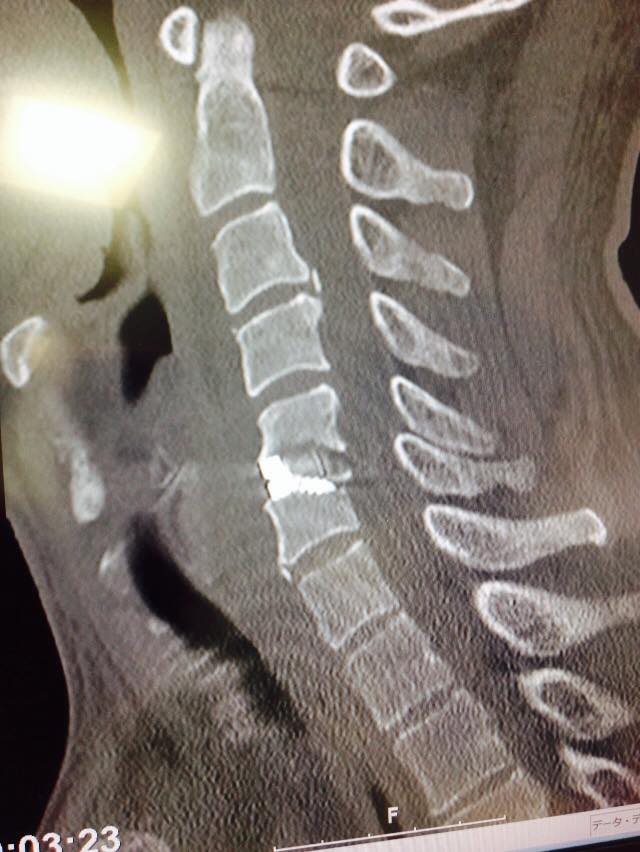

11050861_849659838443938_523163075864166819_n.jpg

11150839_849659771777278_1383166084844027666_n.jpg

11263953_849659701777285_8073529659694470784_n (1).jpg

ざっとこんな感じ(笑)

さてどれくらい腕の力と感覚戻るかなぁ~

それより左の握力関連が辛いなぁ

クラッチ握れるかな?